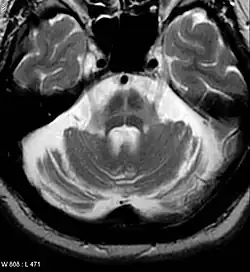

An MRI finding that is seen commonly in Multiple System atrophy. This occurs on the Pons.

The "Hot Cross Bun" sign, found in MSA with MRI

Both MRI and CT scanning may show a decrease in the size of the cerebellum and pons in those with cerebellar features (MSA-C). The putamen is hypointense on T2-weighted MRI and may show an increased deposition of iron in the Parkinsonian (MSA-P) form. In MSA-C, a "hot cross bun" sign is sometimes found; it reflects atrophy of the pontocerebellar tracts that give T2 hyper intense signal intensity in the atrophic pons.

MRI changes are not required to diagnose the disease as these features are often absent, especially early in the course of the disease. Additionally, the changes can be quite subtle and are usually missed by examiners who are not experienced with MSA.